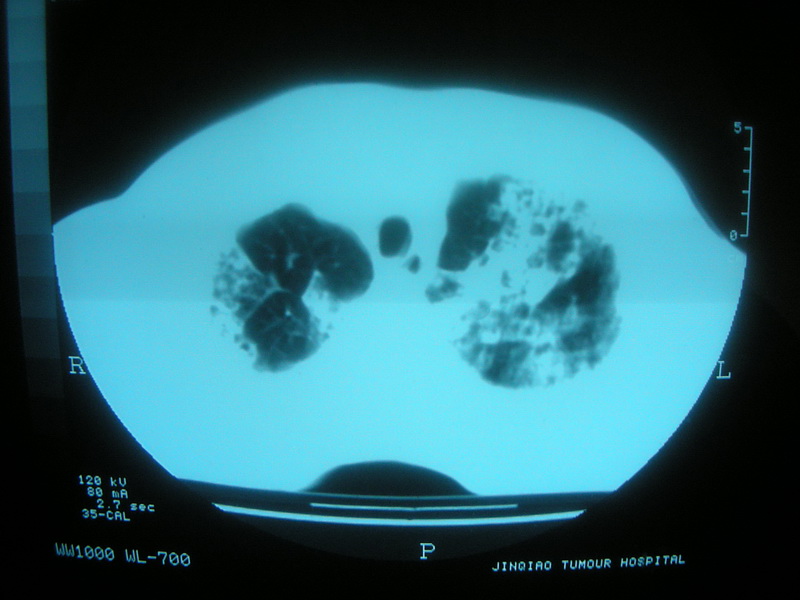

标题: CT11692:男,63岁,糖尿病史15年.抗炎治疗7天,病情 [打印本页]

标题: CT11692:男,63岁,糖尿病史15年.抗炎治疗7天,病情

请老师看看是结核还是炎症?

双肺继发性肺结核伴感染!

双肺继发性肺结核伴支气管播散。

考虑双肺继发性肺结核。